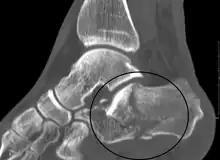

| X-ray of a fractured calcaneus | |

| Diagnostic method | Based on symptoms, X-rays, CT scan[1] |

Conventional radiography is usually the initial assessment tool when a calcaneal fracture is suspected. Recommended x-ray views are (a) axial, (b) anteroposterior, (c) oblique and (d) views with dorsiflexion and internal rotation of the foot. However, conventional radiography is limited for visualization of calcaneal anatomy, especially at the subtalar joint. A CT scan is currently the imaging study of choice for evaluating calcaneal injury and has substituted conventional radiography in the classification of calcaneal fractures.[13] Axial and coronal views are obtained for proper visualization of the calcaneus, subtalar, calcaneocuboid and talonavicular joints.